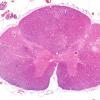

VASCULAR

Infarct - Spinal Cord (6)